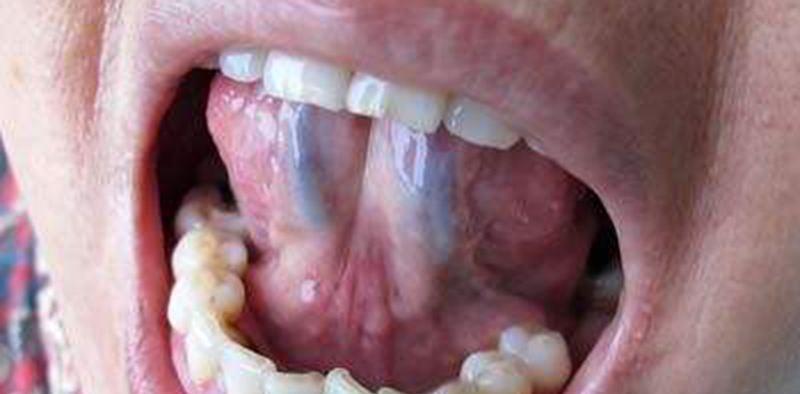

舌头通过经络和身体的五脏相连 , 所以人体的脏腑津液和气血的虚实情况 , 疾病的轻重变化都能通过观察舌头看出来 , 把舌头卷起来 , 我们会发现舌头下面有很突出的青筋 。

有时间的话 , 大家不妨看一下自己舌头下面的青筋是不是很明显 , 其实舌头青筋就是静脉血管 , 静脉血管分布的身体各个部位 , 凡是在身体上看到凸起的青筋都是静脉血管 。

正常情况下颜色是呈浅青色 , 形态并不突出 , 当血循环充沛时 , 舌头青筋颜色会变成淤血的颜色 , 青色比较明显 , 当血液量过大时会出现黑色舌头上的两条筋是人体的经络之一 , 掌管着全身毛细血管系统 。

中医讲究望闻切外 , 可以通过观察舌头轻轻的颜色来判断身体是否出现了问题 , 如果颜色出现偏紫色 , 说明体内寒气和湿气较重 , 如果颜色发黑 , 而且以黑色为点向4周扩散 , 说明体内有炎症或者是某些部位寒气较重 , 如果舌头下的青筋异常粗大 , 而且颜色特别深 , 说明全身的静脉出现了问题 , 有可能是血压升高 , 或者是血液中脂肪浓度较高引起的 。